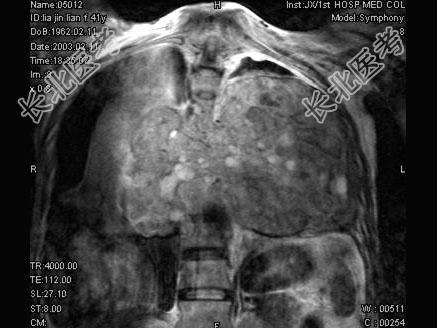

- 单项选择题女,41岁, 胸背部疼痛,肢体活动感觉障碍2年余, MRI检查见T

、T

椎体及附件骨质破坏,并向周围形成巨大肿块影, 呈T1低信号为主,T2加权有多个大小不一圆形混杂高信号, 边界清楚,最可能的诊断是 ( )